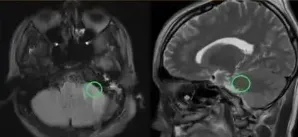

手术按计划进行。巴教授成功为沫沫完成肿瘤全切术,术后患者无新发神经损伤,运动功能未受影响。这一成果得益于这位年轻人超乎寻常的毅力和决心。沫沫如愿为未来清除了一个重大障碍,我们希望他能始终保持这份勇气,坚定前行!